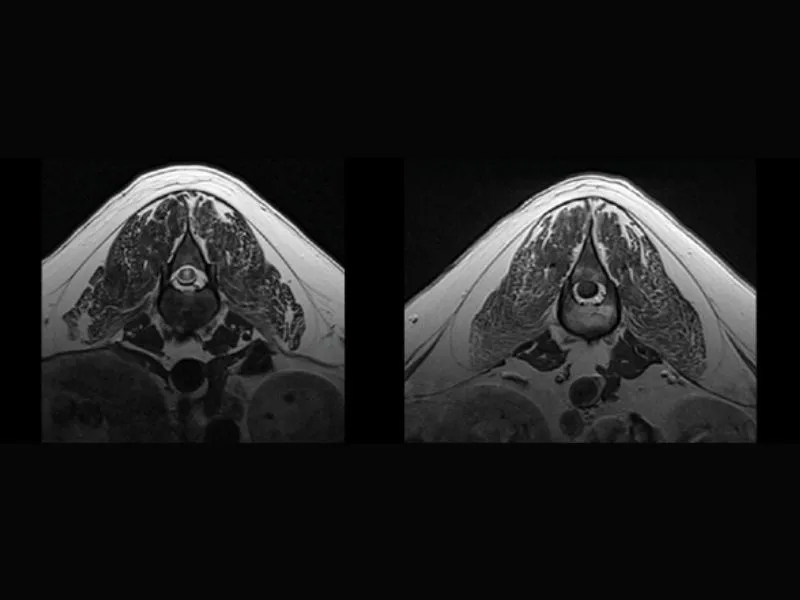

Supreme vet-mr – Transverse T2W with “Propeller” technique